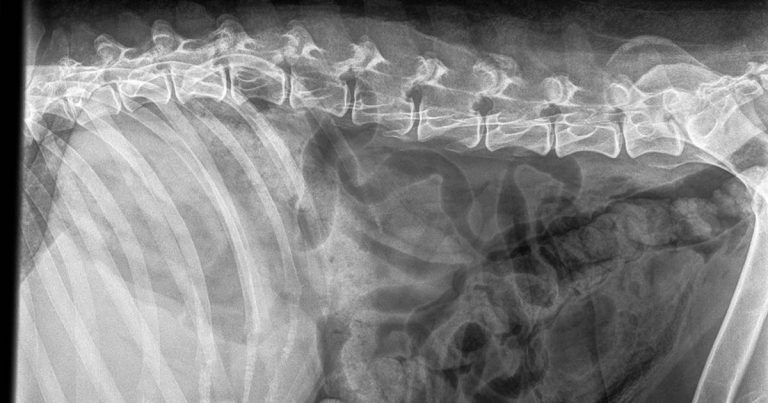

Figure 2. Right lateral plain abdominal radiograph of a dog with emphysematous cystitis. Note the presence of gas in the bladder wall.

Emphysematous cystitis (Figure 2) is caused by infections with gas-forming bacteria – most commonly E coli – and described in sporadic case reports in veterinary literature. Cases have mostly been reported in diabetic and glucosuric patients, but have been described in patients with chronic UTIs and in one patient receiving long-term prednisolone therapy secondary to infection with Clostridium perfringens. Prognosis appears to be good with appropriate antibiotic treatment. Intravesiculal instillation of formalin has also been described as a treatment13.